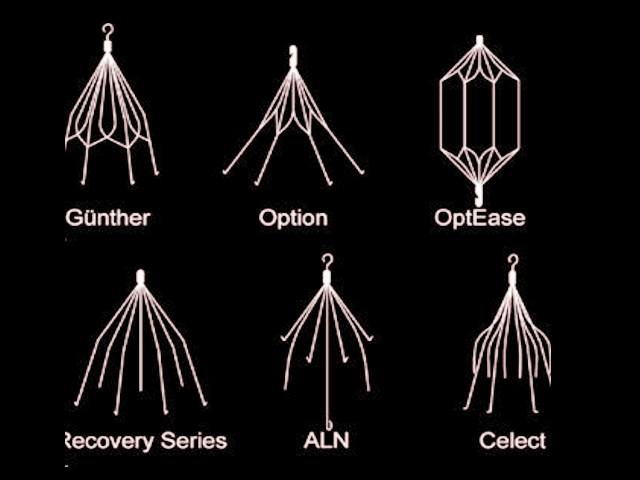

فیلتر ivc قلبی به دستههای دائمی، قابل بازیابی (retrievable)، convertible و bioconvertible تقسیم میشوند. اکثر مدلها از مواد مانند Nitinol یا stainless steel ساخته شدهاند و شکل مخروطی یا cage-like دارند.

مدلهای دائمی:

- Greenfield (Boston Scientific): مدل کلاسیک stainless steel یا titanium، معرفیشده در 1973، با پاتنسی بالا و مناسب برای IVC تا 28 mm.

مدلهای قابل بازیابی (retrievable): - Denali (BD/Bard): پیشرفته، با نرخ بازیابی بالا و کاهش tilt/migration.

- Günther Tulip و Celect/Celect Platinum (Cook Medical): محبوب، با anchoring legs، اما ریسک perforation.

- Option (Argon Medical): مشابه Denali، اما گاهی سختتر بازیابی.

- OPTEASE (Cordis): retrievable تا مدت محدود، cage-like.

مدلهای قدیمیتر Bard (با عوارض بیشتر، منجر به lawsuits): - Recovery, G2, G2 Express, Eclipse, Meridian.

انتخاب مدل بر اساس قطر IVC، مدت نیاز و ریسک عوارض است. تا 2025، تمرکز بر مدلهای با نرخ بازیابی بالا مانند Denali و Celect Platinum است.